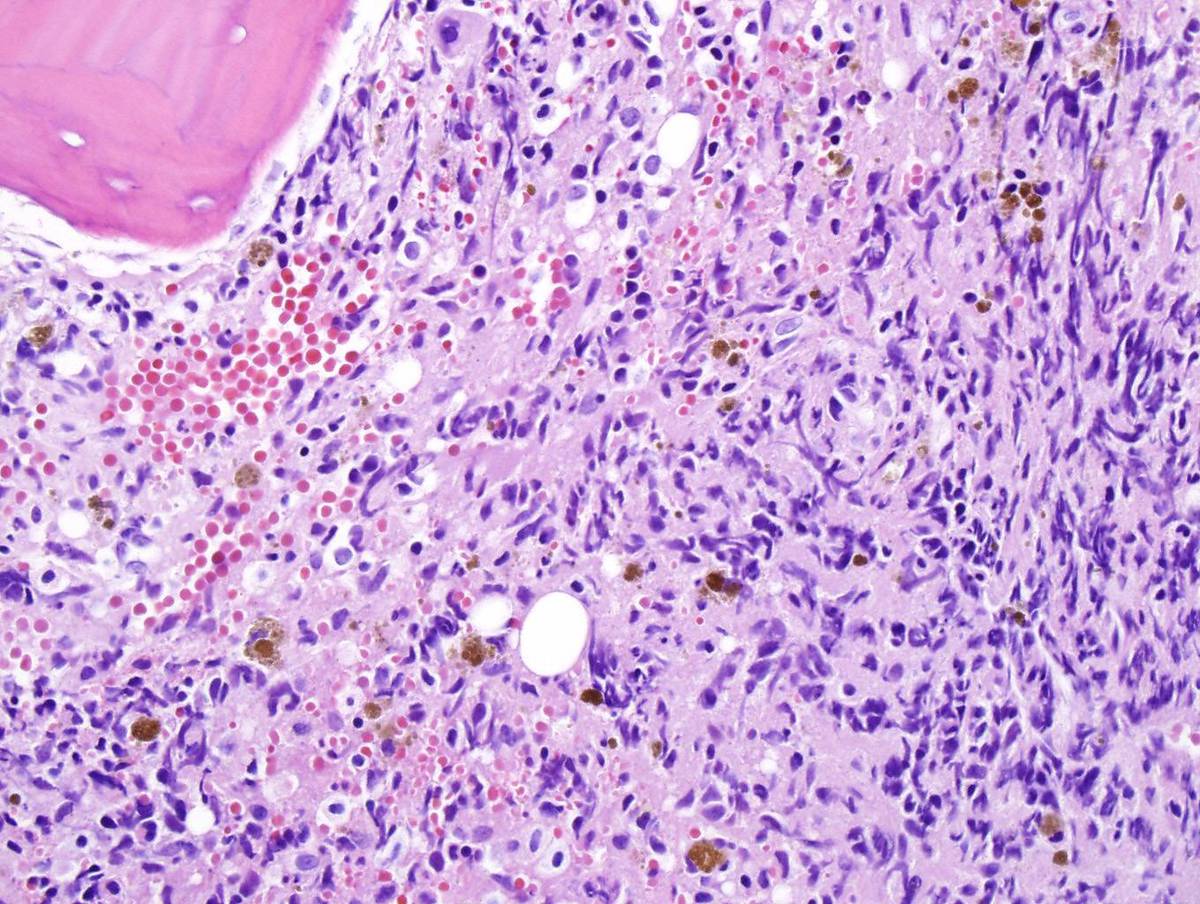

B. Peripheral Blood and First Bone Marrow: Peripheral blood showed mild absolute eosinophilia and mild absolute basophilia. Bone marrow touch inprints showed about 2% blasts, markedly increased eosinophils, eosinophil precursors and increased basophils. Bone marrow core biopsy showed a few areas with sheets of eosinophils and eosinophil precursors and large areas of marked reticulin fibrosis. Megakaryocytes (small and large) were increased.C. Peripheral Blood and Second Bone marrow: Peripheral blood showed numerous blasts. Bone marrow showed approximately 85% large blasts with, moderate N/C raio, prominent nucleoli, and large amount of blue/vacuolated cytoplasm (i.e monoblastic appearance). Core biopsy sections showed sheets of large blasts with moderate N/C raio and prominent nucleoli. Marked reticulin fibrosis was present in some areas.IMMUNOHISTOCHEMISTRY AND FLOW CYTOMETRY

| Bone marrow core biopsy shows sheets of eosinophils and eosinophil precursors. | ![]() |

| Bone marrow core biopsy with areas of marked fibrosis. | ![]() |